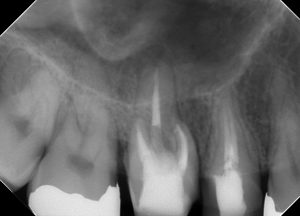

(術直後のレントゲン)

術後の仕上がりには問題は無い。

そして、支台築造もラバーダム防湿化で行うことが重要だ。